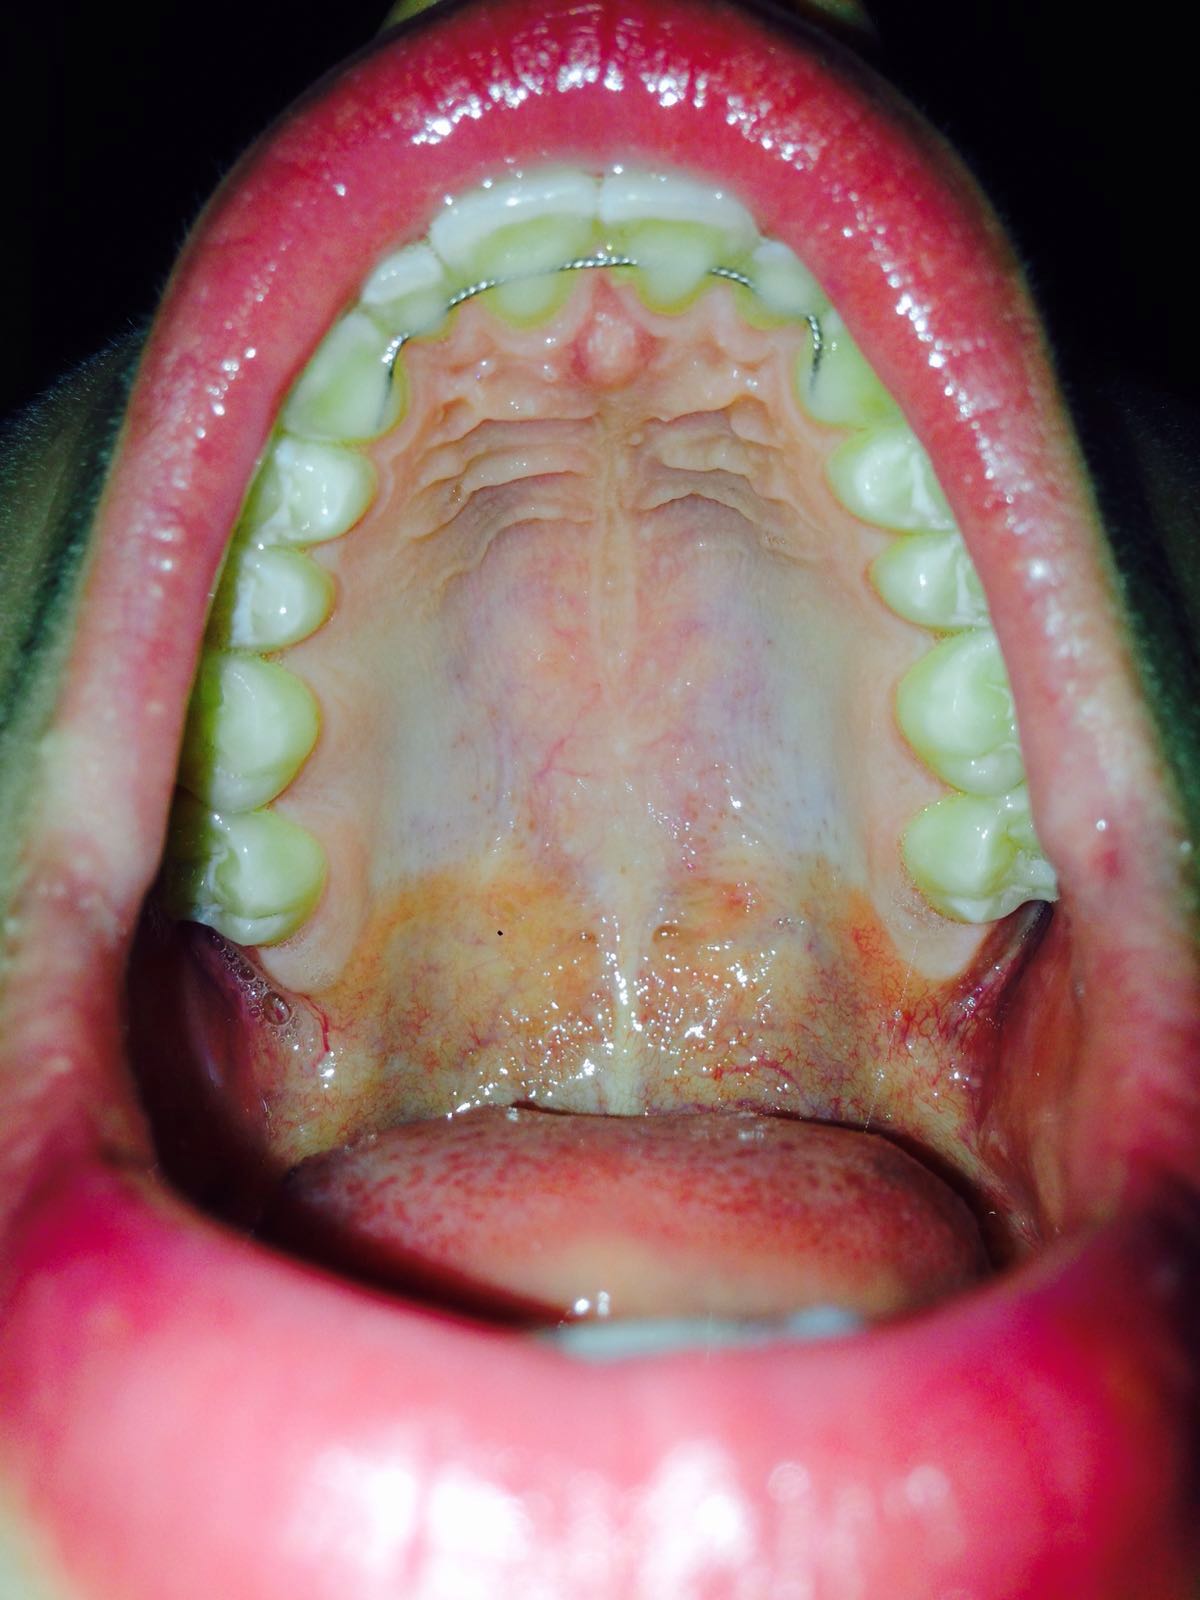

Eine Schwellung des Zahnfleisches ist ein Anzeichen für eine Entzündung. Hierbei wird Flüssigkeit im Gewebe eingelagert, welches durch eine Allergie oder Infektion hervorgerufen werden kann. Weitere Auslöser können sein: ein traumatischer Zahnunfall oder eine Verletzung. Ödeme. Blutungen. Fisteln am Zahnfleisch.. Auch eine Schwellung der betroffenen Areale (z. B. am Zahnfleisch, Gaumensegel, Gaumenzäpfchen, den Gaumenmandeln oder dem allgemeinen Oberkiefer) ist ein klassisches Entzündungszeichen. Begleitende Bläschen können auf einen Virenbefall oder Aphthen hindeuten. Gelbweiße Eiterherde weisen normalerweise auf eine Bakterienbesiedlung hin.

Schmerzlose Schwellung des Gaumens Behandlungsalgorithmus und Differenzialdiagnose

Ein geschwollener Gaumen bereitet nicht nur Schmerzen, sondern führt auch oftmals dazu, dass nicht mehr richtig gegessen werden kann. Es gilt daher, den geschwollenen Gaumen möglichst schnell zu behandeln und dadurch zu einer schnellen Genesung zu führen. Um zu verstehen, wie ein geschwollener Gaumen überhaupt entsteht, muss zunächst auf die Ursachen. Um diese soll es […]. We accept most insurance, Worker's Compensation and affordable payment plans so financial concerns won't stand in the way of getting the care you need. Call us at (304) 263-4927 or email us today to schedule an appointment and take the first step on your journey to optimal health.